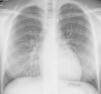

A 19-year-old girl was admitted in hospital after several episodes of dyspnea on mild exertion, hypoxemia, low fever and non productive cough accompanied by hemoptysis twice since she was 10. In one of those prior episodes she was admitted into an intensive care unit under invasive ventilation. On physical examination she was pale, tachycardic and polypneic with diffuse rales in auscultation. Chest X-ray revealed bilateral diffuse alveolar infiltrates, mainly in lower fields. Laboratory investigations presented a severe normocytic normochromic anemia with hemoglobin reaching the level of 7.6g/dl and leukocytosis with neutrophilia. In the first three bouts the presumptive diagnostic was that of recurrent community-acquired pneumonia, however, given the low impact of the antimicrobials, absence of microbiological isolations and presence of hemoptysis and anemia, the clinical suspicion was eventually redirected to diffuse alveolar hemorrhage (DAH).

However, in May 2016, after a pharyngitis she developed another hemorrhagic flare with diffuse infiltrates in chest X-ray (Fig. 2) associated with hypoxemia, anemia, tiredness and dyspnea (mMRC grade 2). She was 48h under observation on a short-stay admission ward and intravenous corticotherapy was initiated. She went home under a course of prednisolone 0.5mg/kg/day for 12 weeks gradually reduced, keeping hydroxychloroquine 400mg/day. Due to the persistence of hemorrhagic activity, azathioprine was introduced as a corticosteroid-sparing agent, maintaining prednisolone in low dose, hydroxychloroquine and inhaled budesonide.